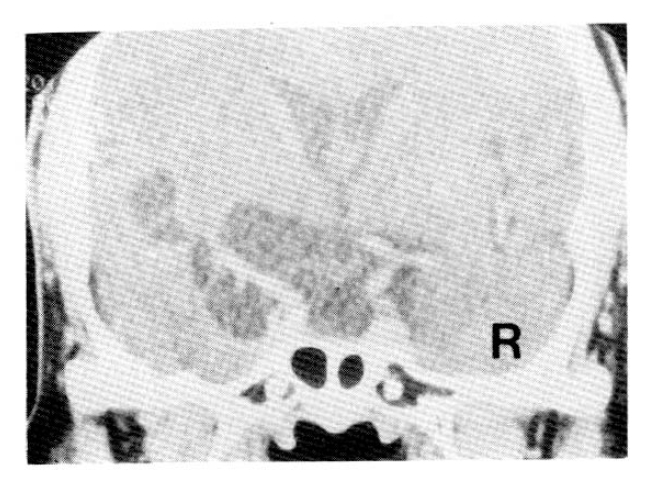

Fig. 1.

Coronal CT scan of the sella with IV contrast infusion: multilobulated cystic lesion in the suprasellar cistern and the left sylvian cistern with extension into the pituitary fossa. A thin rim of the compressed pituitary gland is noted.

Six moths prior to admission, she had once visited a private clinic because of headache. She refused the recommended brain CT scan, but took some medicine prescribed by the clinic. She came to Yonsei University Hospital with a worsened headache and aggravated dizziness. Routine serum tests and blood counts were all in the normal limits. Examination of stool was negative. Examination of CSF showed an opening pressure of 130mmCSF, 9 leukocytes/mm3, a protein level of 30mg/dl and a glucose level of 49mg/dl. Routine bacteriologic cultures were all negative. A CT scan showed multiple low-density cystic lesions in the suprasellar and left sylvian cisternae compatible with empty-sella syndrome (Fig. 1). In order to evaluate the communication between the cisternae and the suprasellar cyst, a metrizamide CT scan was performed, but it revealed no communication (Fig. 2). Enzyme linked immunosorbent assay (ELISA) for anti-cysticerci IgG in the patient’s CSF and serum gave titers of 1.14 and 0.95, respectively, consistent with active infection (Table 2). There were no abnormal neurological findings. In the combined pituitary stimulation test, the reserve capacities were all prompt except for the TSH response which was blunted (Table 1). The basal serum T3 level was 104.75ng/dl. T4 5ug/dl, fT4 0.86ng/ml, estradiol 25 pg/dl and prolactin 4.31ng/ml.